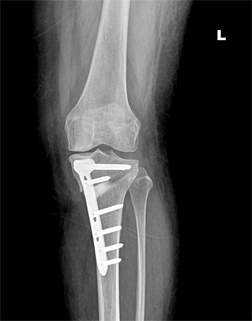

관절염의 수술적 치료로 인공관절 수술이 가장 흔하나, 인공관절수술은 일을 하고 운동을 해야하는 젊은 사람들에게는 시행하기 어려운 단점이 있습니다. 그래서 근위경골 절골술은 체중부하를 관절염이 생기지 않는 쪽으로 옮겨주는 방법입니다.

경골 교정 절골술 전

경골 교정 절골술 후